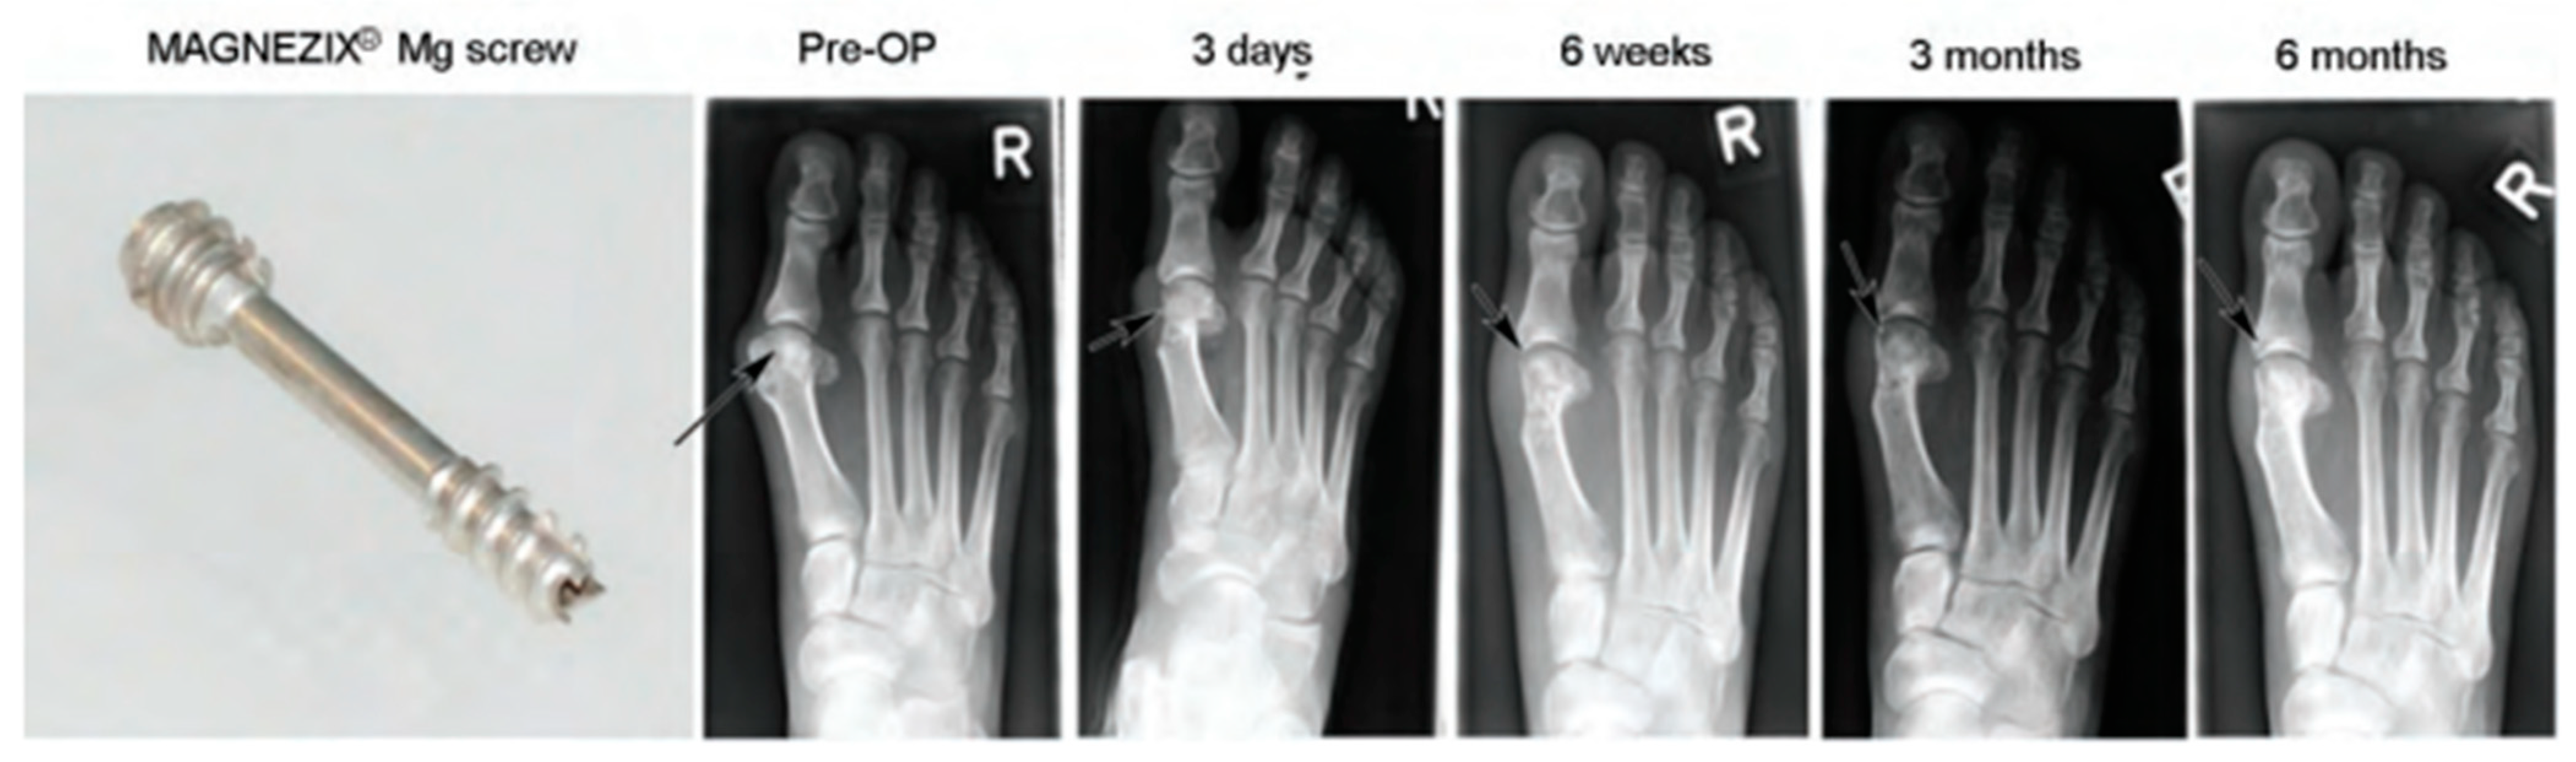

- Windhagen, H.; Radtke, K.; Weizbauer, A.; Diekmann, J.; Noll, Y.; Kreimeyer, U.; Schavan, R.; Stukenborg-Colsman, C.; Waizy, H. Biodegradable Magnesium-Based Screw Clinically Equivalent to Titanium Screw in Hallux Valgus Surgery: Short Term Results of the First Prospective, Randomized, Controlled Clinical Pilot Study. Biomed. Eng. Online 2013, 12, 62. [Google Scholar] [CrossRef] [PubMed]

- Plaass, C.; Ettinger, S.; Sonnow, L.; Koenneker, S.; Noll, Y.; Weizbauer, A.; Reifenrath, J.; Claassen, L.; Daniilidis, K.; Stukenborg-Colsman, C.; et al. Early Results Using a Biodegradable Magnesium Screw for Modified Chevron Osteotomies. J. Orthop. Res. 2016, 34, 2207–2214. [Google Scholar] [CrossRef]

- Seitz, J.M.; Lucas, A.; Kirschner, M. Magnesium-Based Compression Screws: A Novelty in the Clinical Use of Implants. JOM 2016, 68, 1177–1182. [Google Scholar] [CrossRef]

- Lee, J.W.; Han, H.S.; Han, K.J.; Park, J.; Jeon, H.; Ok, M.R.; Seok, H.K.; Ahn, J.P.; Lee, K.E.; Lee, D.H.; et al. Long-Term Clinical Study and Multiscale Analysis of in Vivo Biodegradation Mechanism of Mg Alloy. Proc. Natl. Acad. Sci. USA 2016, 113, 716–721. [Google Scholar] [CrossRef]

- Plaass, C.; von Falck, C.; Ettinger, S.; Sonnow, L.; Calderone, F.; Weizbauer, A.; Reifenrath, J.; Claassen, L.; Waizy, H.; Daniilidis, K.; et al. Bioabsorbable Magnesium versus Standard Titanium Compression Screws for Fixation of Distal Metatarsal Osteotomies—3 Year Results of a Randomized Clinical Trial. J. Orthop. Sci. 2018, 23, 321–327. [Google Scholar] [CrossRef]